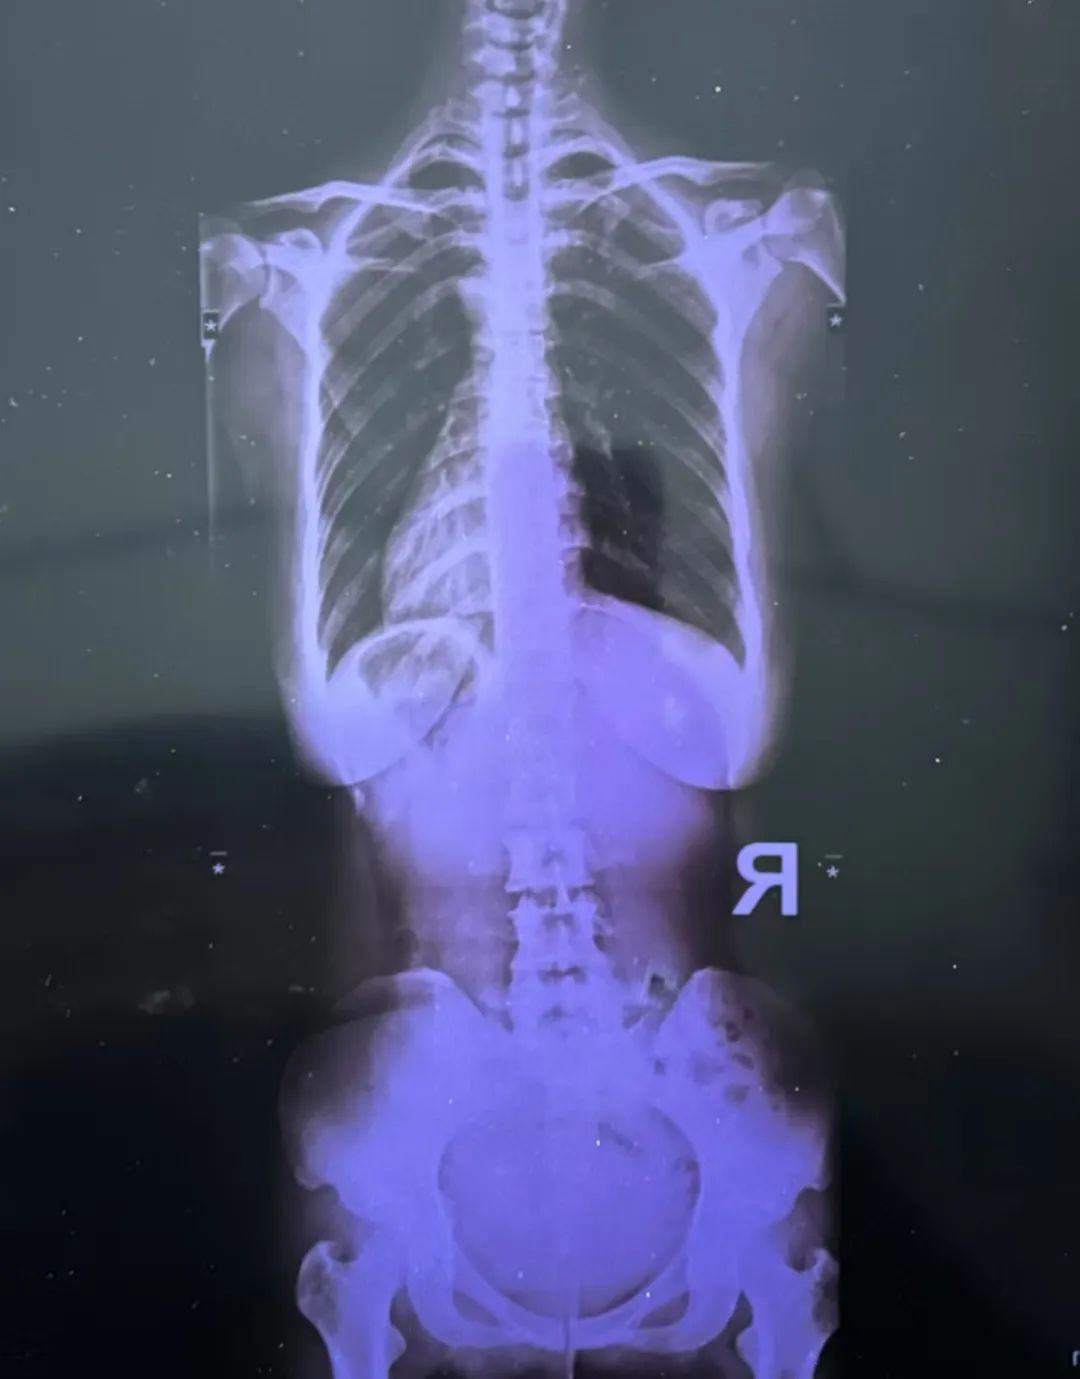

最近又疼起來嚴重影響正常生活,她前往醫院就診,結果查出了脊柱側彎11°,骨盆旋移,骶髂關節半脫位,由于這些導致頸肩,后背,腰部肌群代償出現問題,從而出現腰痛,后背痛,肩膀痛!

蘇鴻凱醫生根據王女士的具體情況,為王女士制定針對性治療方案,在治療中采用正骨手法復位,在配合結構針法治療,來調節肌肉功能使恢復平衡。